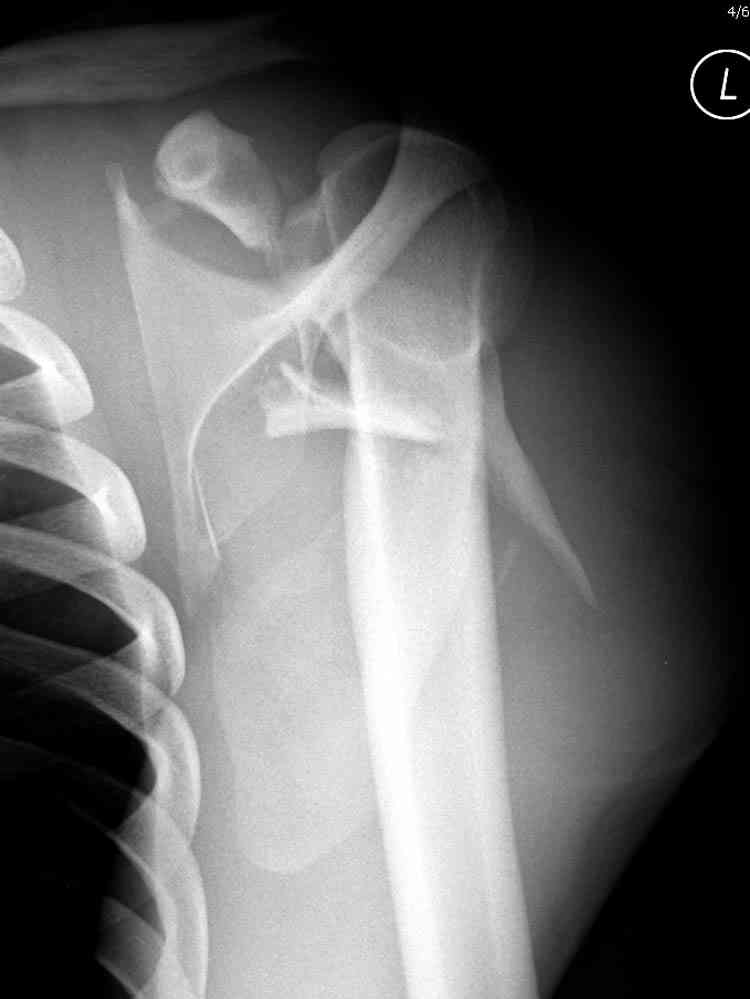

Никита, поздравляю с хорошей репозицией перелома

ключицы.

Для решения насчет оперативного вмещательства на лопатке сперва надо определиться с обьязательными ренгенологическими исследованиями, не менее трех стандартных проекций: прямая, аксиллярная и в позиции виде “Y”.

Прямую снимают под углом в 35 градусов от центра и вид “Y” в 90 градусов к нему. Несмотря на неудобства, больному необходимо сделать

аксиллярный снимок.

При отсутствии соединения верхнего пояса с телом из-за перелома ключицы и шейки лопатки имеется состояние "floating shoulder", как в аналогии повреждения около коленного сустава "floating knee" при переломах костей выше и ниже коленного сустава.

В таких случаях, когда нет больших смещений на стороне суставной поверхности, и нет необходимости операции на лопатке, тогда ограничиваются фиксацией только ключицы, то есть фиксируется верхняя конечность к туловищу через ключицу...